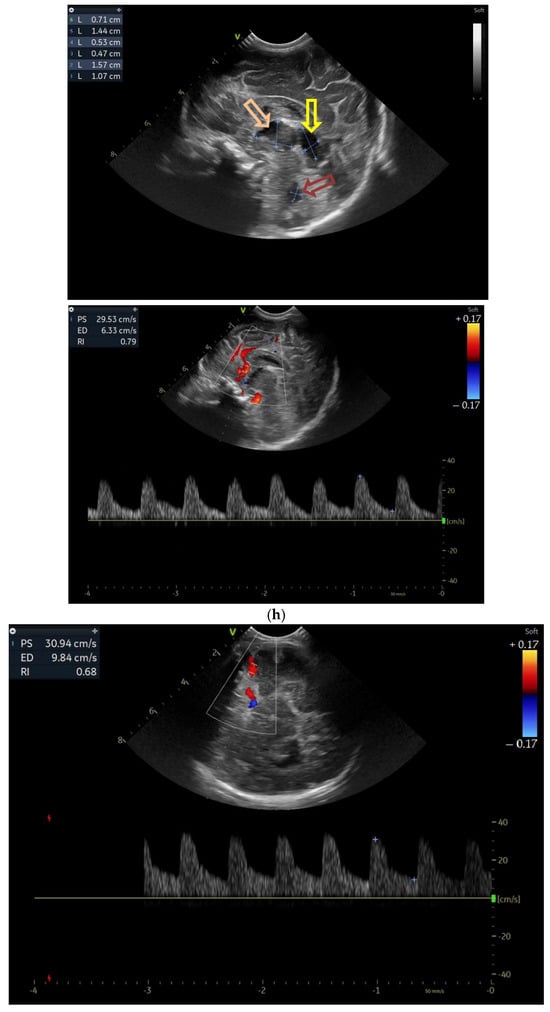

Five weeks after birth, the patient presented for the first cranial ultrasound examination, which revealed enlarged ventricles and the presence of a hyperechoic image in the right frontal lobe, suggestive of calcifications. The parenchymal tissue was reduced (Figure 4a–d). The anterior fontanelle was wide, with large sutures. The neurological assessment showed that the infant could keep eye contact and would also hold its head during the traction-to-sit maneuver but was not able to lift its head while in the prone position. The passive tone assessment showed the “scarf sign”, with the elbow at the midline and a popliteal angle range for both legs of 90–100°. Deep tendon reflexes were present. The general movement (GM) assessment revealed a poor repertoire pattern with minimal mobility in the lower limbs. Treatment for Toxoplasma was initiated.

Figure 4.

(a) Cranial ultrasound. Coronal view. Lateral ventricles and third ventricle enlargement. L1, L2—Levine index measurement. L3, L4—posterior horn of the lateral ventricles’ width measurement. L5—third ventricle width measurement (personal image collection). (b) Cranial ultrasound. Sagittal view. Enlarged third and fourth ventricles. L1, L2—third ventricle measurements. L3, L4—fourth ventricle measurements (personal image collection). (c) Cranial ultrasound. Sagittal view. Enlarged lateral ventricles. Up—left ventricle. Down—right ventricle (personal image collection). (d) Cranial ultrasound. Coronal view. Punctuate hyperechoic images were observed in the right lobe (personal image collection). (e). Up left—MRI T1 sequence. Up right—MRI T2 sequence—susceptibility weight imaging (SWI). Down—CT scan. Transversal view. Yellow arrows—multiple calcifications can be seen in the CT scan (personal image collection). (f) Cranial ultrasound. Coronal view. Lateral ventricles. L1, L2—Levine index measurement. L3, L4—anterior horn width measurement. Blue arrow—intraventricular shunt (personal image collection). (g) Cranial ultrasound. Sagittal view. Thalamo-occipital distance measurements. Up—right ventricle. Down—left ventricle (personal image collection).

At six weeks after birth, an MRI scan was performed, while a CT scan was performed at 14 weeks of life, both providing valuable information regarding the sequelae of Toxoplasmosis (Figure 4e). Even though a few signs were observed on the MRI, the CT scan better outlined the presence of the parenchymal calcifications. A neurosurgical intervention was intended, a ventricle puncture was performed, and a shunt was placed in the right ventricle. The cranial ultrasound at two months of life did not show notable improvements, however (Figure 4f,g). The neurological examinations showed axial hypotonia and limb hypertonia.